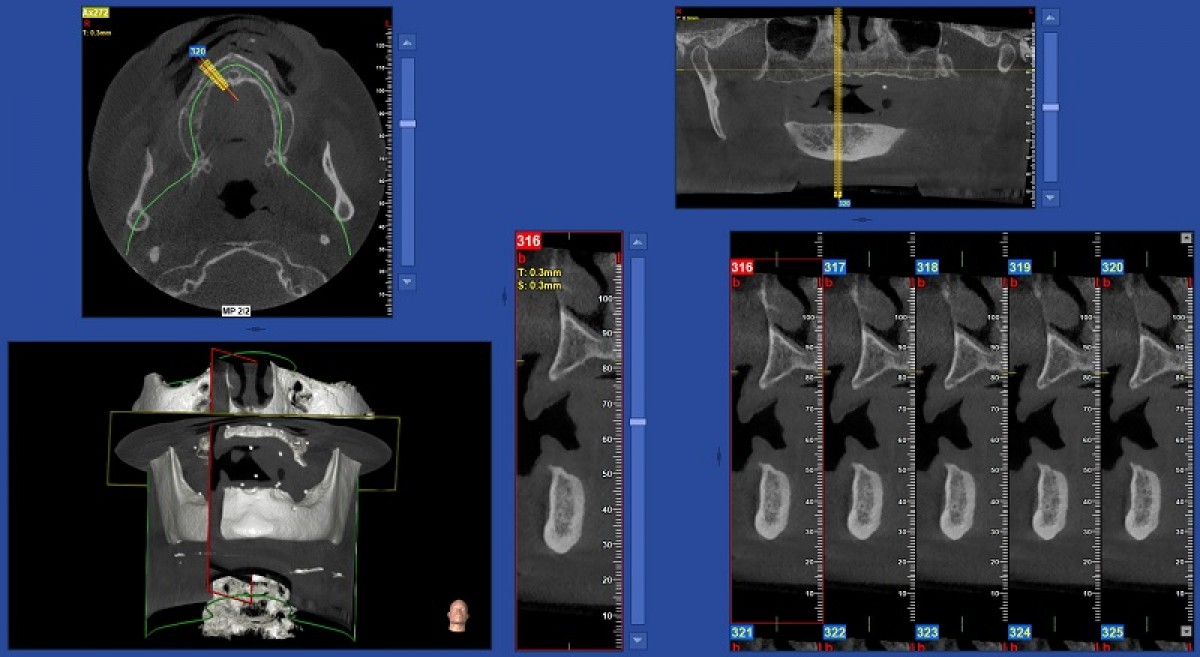

In this particular case, the computerized cephalometric analysis performed using the Nemoceph (Nemotec) software, highlighted on the lateral projection a skeletal class 1, a brachyfacial type and pathological positioning of the upper and lower incisors; the latter appeared retro-positioned compared to their respective skeletal bases (incisive overbite) and linguo-inclined (insufficient torque). This situation gave rise to the so-called "incisor wall" which could compromise correct occlusal contact and proper functioning of the temporomandibular joints. It also influences the aesthetics of the smile. Cephalometric analysis on the frontal plane showed a good transverse relationship between the upper and lower jaws and confirmed the rightward deviation of the lower midline. To plan the orthodontic treatment, we performed a cephalometric VTO to simulate the correct positions that the incisors should reach at the end of the course of treatment (fig. 5).

The cephalometric VTO allowed us to identify the exact movements the incisors need to make in the sagittal and vertical planes. To complete the three-dimensional treatment planning, the virtual set-up was used. The dental arches were further scanned using the Trios (3Shape) scanner (fig. 6).